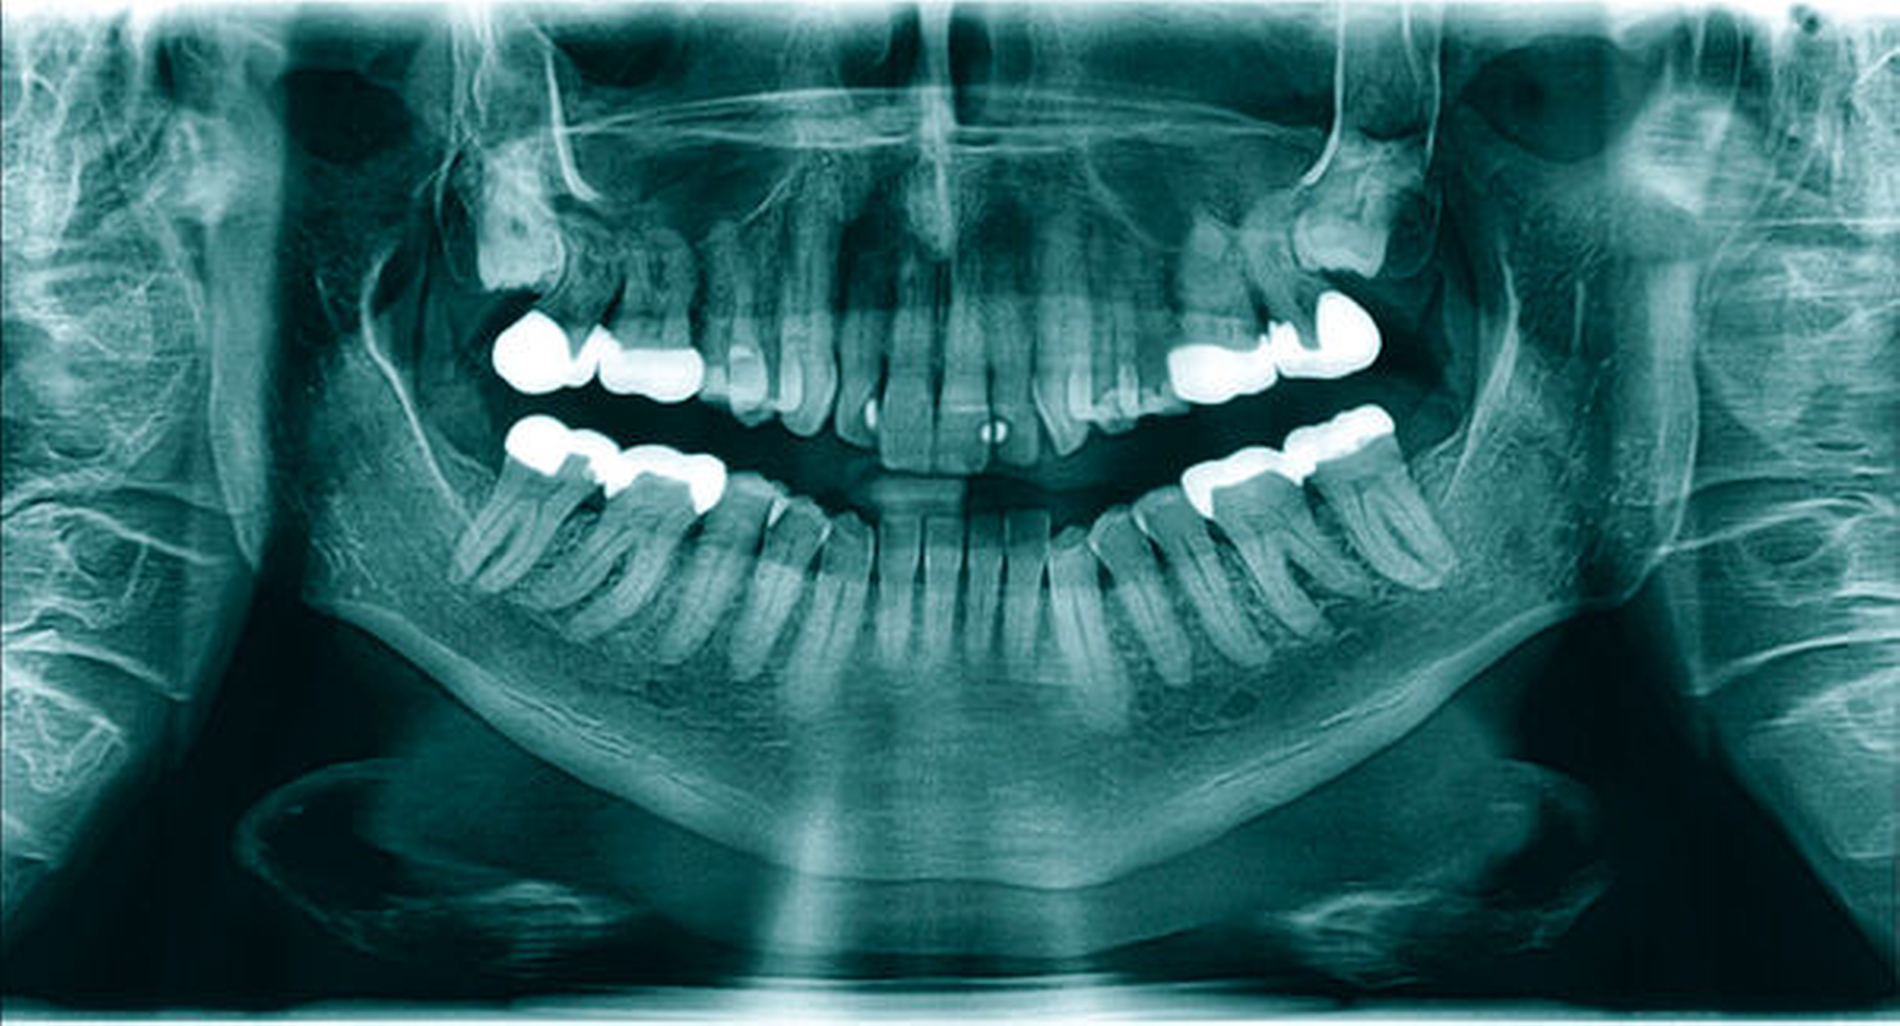

Nebenbefundlich zeigte sich in der PSA (Abbildung 1) im Bereich des rechten Kieferastes eine circa 10 mm x 6 mm große, klar begrenzte, knochendichte Opazität. Diese Opazität erschien als am Rand opak verdichtete und nicht infiltrierende Struktur, die mit keiner erkennbaren dentogenen oder nicht-dentogenen Struktur direkt korrelierte. Auf einer zum Vergleich vom Hauszahnarzt angeforderten PSA, die etwa neun Jahre zuvor erstellt wurde, ist ein vergleichbarer Befund zu sehen (Abbildung 2).